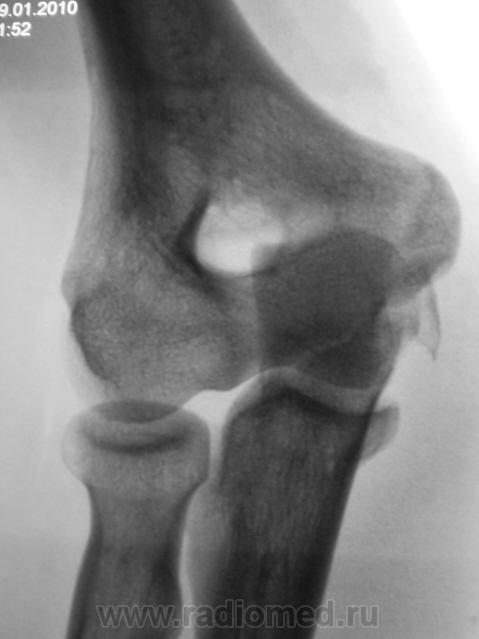

Травма.     Пациент направлен на рентгенографию локтевого сустава.

Перелом локтевого отростка - на операцию

Если рассуждать с точки зрения только диагностики перелома - нет, так как перелом хорошо виден и на стандартных проекциях. С точки зрения дальнейшей лечебной тактики - да. Так как косые проекции выявили безусловную необходимость оперативного лечения.